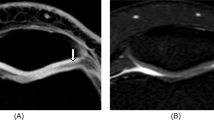

On FS PDw TSE MR imaging, intact cartilage appeared with low to intermediate signal (Fig. 1). High signal intensity of joint fluid and cartilage edema assisted in the visualization of cartilage contour irregularities and internal derangement (Fig. 2, 3, 4). Fifty-eight findings were true-positive, six false-negative (3 grade 1a, 1 grade 1b, 1 grade 2a, 1 grade 2b), two false-positive, and 90 true-negative (Table 1). Sensitivity, specificity, positive predictive value, negative predictive value, and accuracy were 91%, 98%, 96%, 94%, and 95%, respectively. The correlation between arthroscopy and FS PDw TSE for grading and sizing cartilage lesions was significant in all compartments (Tables 2, 3).

A 32-year-old woman with an arthroscopically proven grade 2b lesion on the medial patellar facet (arrows) in the transverse plane. On WE 3D FLASH (A) the lesion was graded as 2a. The lesion is correctly graded on FS PDw TSE (B) MR imaging. Note that on FS PDw TSE MR imaging the surface irregularities can be visualized better due to the arthrographic effect of the bright joint fluid. A WE 3D FLASH: 28/11 ms, flip angle 40°. B FS PDw TSE: 3433/15 ms, flip angle 180°

A 44-year-old woman with an arthroscopically proven grade 3a lesion on the patella and a grade 3b lesion on the trochlear groove in the sagittal plane (arrows). With WE 3D FLASH (A) the patellar lesion was underestimated as grade 2b. Correct grading was performed on FS PDw TSE (B) MR imaging. Note that both lesions are better depicted on FS PDw TSE MR imaging due to the arthrographic effect and the signal changes due to cartilage and bone edema. A WE 3D FLASH: 28/11 ms, flip angle 40°. B FS PDw TSE: 3433/15 ms, flip angle 180°